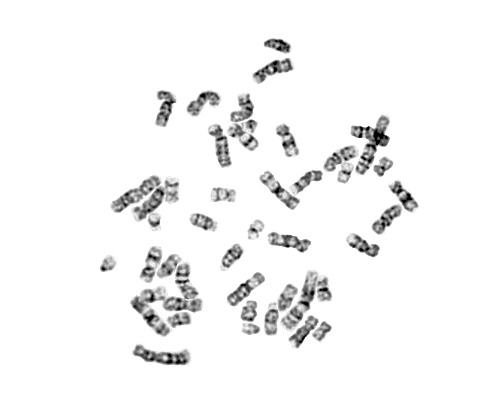

中期分裂相原图

● 基于人工智能提供高效、精准的染色体核型分析功能,可用于外周血、羊水、骨髓等多种样本类型。

● 兼容PNG、JPG格式图片,单张图片进行一键快速分析,自动计数+自动排列仅需1.5s,准确率≥90%

染色体图像自动筛选优化,一键切割计数